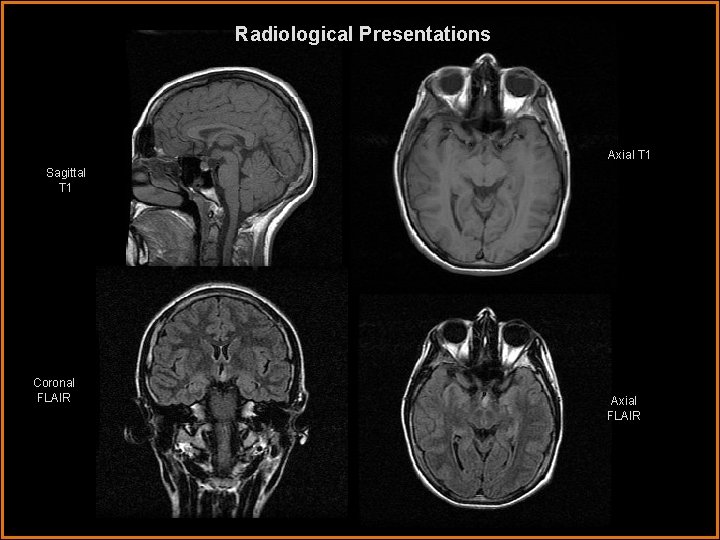

Radiological Presentations Axial T 1 Sagittal T 1 Coronal FLAIR Axial FLAIR

Findings and Differentials Findings: MRI reveals a well-circumscribed mass eccentrically located in the region of the hypothalamus. The mass is iso-intense to gray matter on T 1 weighted images and hyperintense to gray matter on T 2 weighted images. Post-contrast images demonstrate no significant enhancement. Differentials: • Craniopharyngioma • Optic glioma • Hypothalamic hamartoma

Discussion Patients typically present with precocious puberty. Other symptoms include visual disturbances and the characteristic “gelastic seizure”, or laughing seizure. These masses are homogeneous and iso-intense to gray matter on T 1, and hyperintense to gray matter on T 2 imaging. They do not enhance. The anatomic location together with the signal characteristics is strongly suggestive of the diagnosis. The optic nerves and chiasm are separate from the mass, excluding an optic nerve glioma. Craniopharyngiomas often have calcifications, cystic components and hemorrhage, a feature lacking in these hamartomas. Hyypothalamic gliomas typically enhance after contrast. The long term stability with failure to grow and continued lack of enhancement would support the diagnosis of hypothalamic hamartoma. Shah P, Patkar D, Patankar T, Shah J, Srinivasa P, Krishnan A. MR imaging features in hypothalamic hamartoma: a report of three cases and review of literature. J Postgrad Med 1999; 45: 84 -6